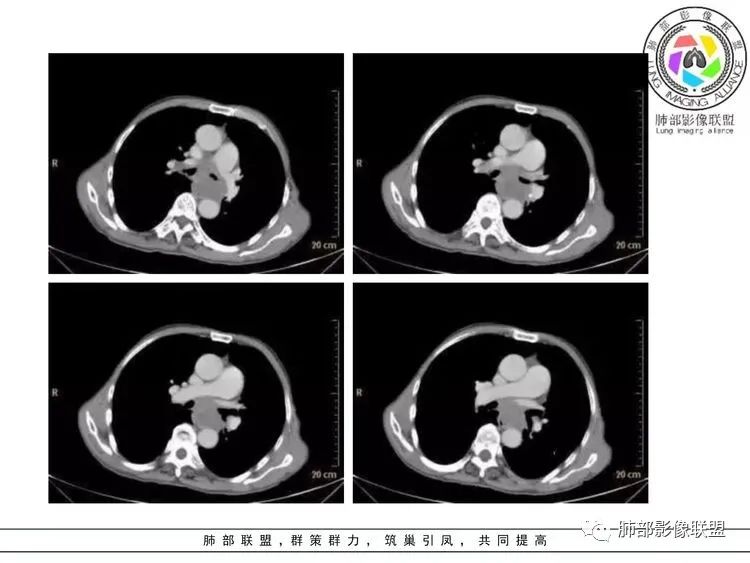

套细胞淋巴瘤( mantle cell lymphoma,MCL) 是一种伴有特征性的 t(11;14)( q13;q32) 易位的成熟B 细胞淋巴瘤,肿瘤细胞通常表达 cyclin D1、CD5 和SOX11[ 1-2] 。 占 非 霍 奇 金 淋 巴 瘤 ( non-Hodgkin lymphomas, NHL) 的 3 ~ 10%。

MCL是一种起源于淋巴结滤泡套区内的小B细胞,在2000年WHO分类中被作为一类独立的疾病而命名为MCL,既往文献报道。其特点为老年男性多见,就诊时多为疾病晚期,75%~100%表现为广泛淋巴结受侵,结外病变发生率较高。

MCL 好发于淋巴结,大多数患者就诊时临床分期为Ⅲ~ Ⅳ期,多伴有淋巴结外侵犯。 MCL是一种非常独特的病理类型,一方面按照其侵袭性的生物学行为和自然史应归为侵袭性NHL,而另一方面,它对治疗的反应类似惰性淋巴瘤(indolent lymphoma),采用目前的标准治疗方法是不可治愈的。常规治疗很难治愈, 患者的中位生存时间仅为 3 ~ 5 年,甚至有些复发难治患者总生存时间仅为1 ~ 2年 。

MCL的CT表现为分布无规律的全身多区域淋巴结受侵,少有单一区域淋巴结受累,结外器官受侵多见;MCL有一般NHL淋巴结受累基本CT表现,平扫CT表现为病变密度均匀,受累淋巴结区内呈融合状生长,边界清楚,增强后病灶呈均匀、中等强化,一般病变内无低密度坏死区。确诊需要病理及免疫组化,根据肿瘤组织形态学和免疫组织化学 CD5 及cyclin D1 的表达绝大多数 MCL 可做出明确病理诊。